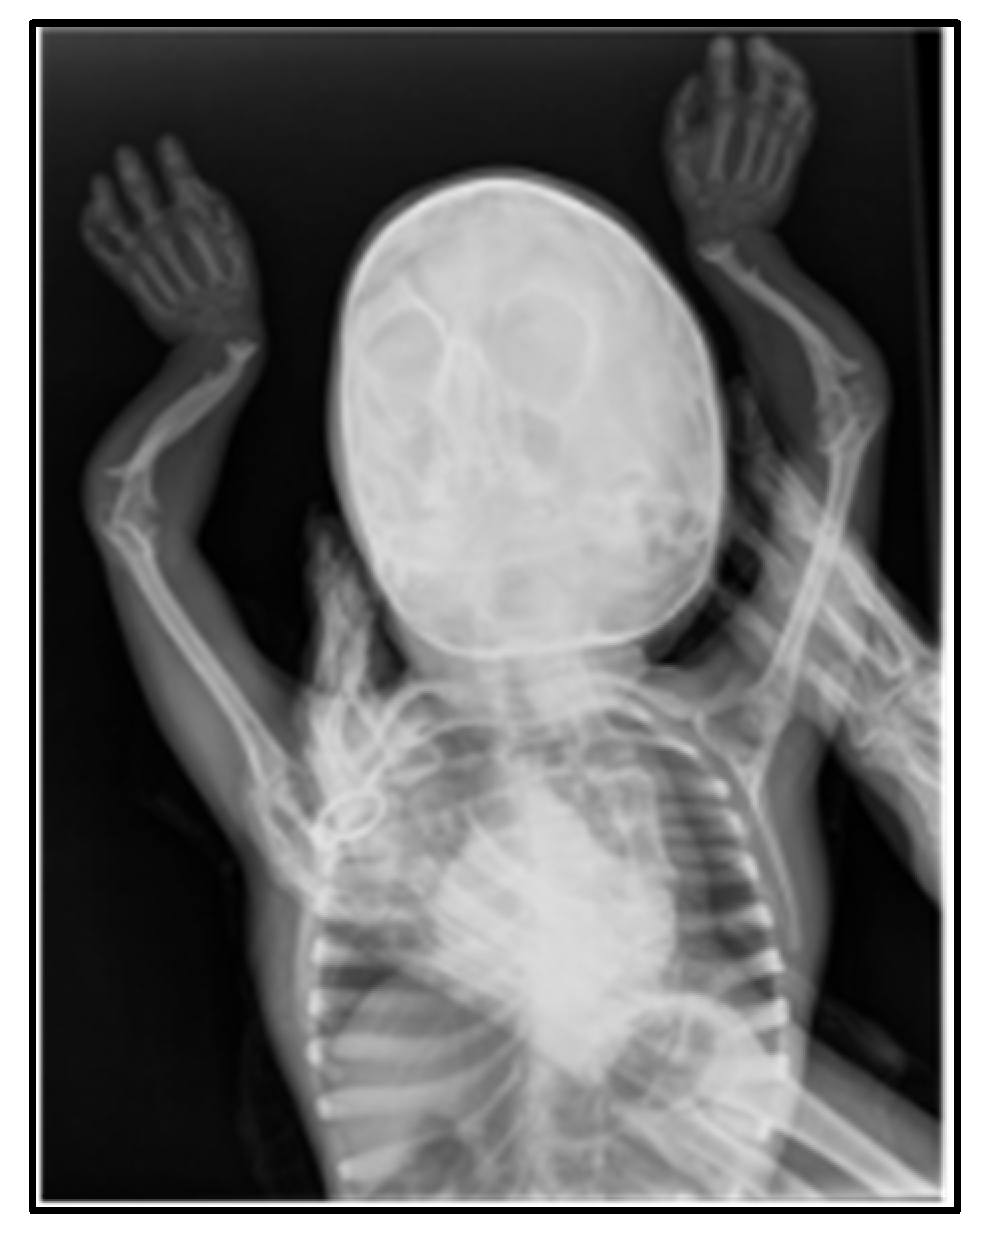

X-Rays

| 2014 (year of patient’s birth) | Slightly blurred coronal sutures in the middle third. Sella turcica is normal in size. Dysmorphic appearance of the orbits. | Absence of carpal ossification nuclei, corresponding to newborn bone age. Altered appearance of the distal radioulnar metaphyses, with widening and deepening of their concavities—rickets suspected? | |||

| 2015 | Oval transparent zones (possible lack of mineralization or osteolysis?) in the parieto-occipital and frontal areas. | Suggestive of rickets: absence of carpal growth nuclei, osteotransparency, curved diaphyses with prominent, widened metaphyses (“champagne glass” shape), no visible bone cortex in the forearm bones. | Cortex not visible in the lower limbs, particularly in the femoral region. | ||